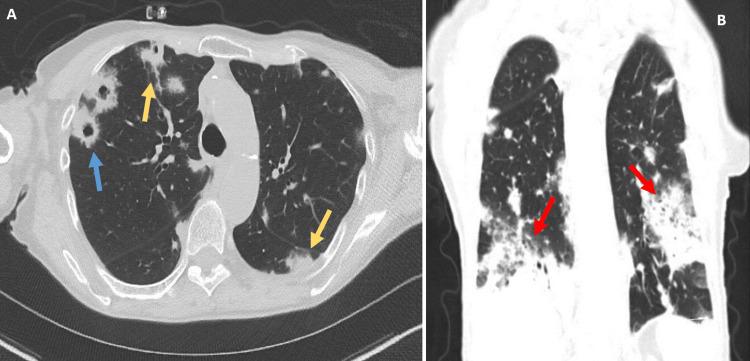

This is a case of a 92-year-old female with multiple hospitalizations for dyspnea on exertion and hypoxemia. Her symptoms were initially thought to be secondary to pneumonia, and on subsequent admission, culture-negative endocarditis. A computed tomography (CT) of the chest was remarkable for numerous bilateral lung nodules of varying size, some of which had a cavitary appearance raising concern for septic emboli. While a transthoracic echo was unremarkable, a transesophageal echo found a small 3 mm echodensity at the tip of the right coronary leaflet of the aortic valve and a possible mobile echodensity on the tricuspid valve leaflet. These findings further supported a clinical diagnosis of endocarditis with septic emboli in the lungs. Initial bronchoscopy yielded an unremarkable biopsy and a bronchial alveolar lavage with the growth of . During a subsequent hospitalization, a repeat bronchoscopy with transbronchial biopsy revealed a final diagnosis of invasive pulmonary mucinous adenocarcinoma. This case highlights a unique presentation of mucinous adenocarcinoma of the lung initially masquerading as septic emboli, resulting in a delay in the final diagnosis.

这是一例92岁女性患者,因劳力性呼吸困难和低氧血症多次住院。她的症状最初被认为继发于肺炎,随后入院诊断为血培养阴性的心内膜炎。胸部计算机断层扫描(CT)显示双侧有许多大小不一的肺结节,其中一些有空洞形成,令人担心是脓毒性栓子。经胸超声心动图检查无异常,但经食管超声心动图发现主动脉瓣右冠状动脉瓣叶尖端有一个3毫米的小回声密度,三尖瓣叶上可能有一个可移动的回声密度。这些发现进一步支持了伴有肺部脓毒性栓子的心内膜炎的临床诊断。初次支气管镜检查活检结果无异常,支气管肺泡灌洗培养出……。在随后的一次住院期间,再次进行支气管镜检查并经支气管活检,最终诊断为浸润性肺黏液腺癌。该病例突出了肺黏液腺癌一种独特的表现形式,最初伪装成脓毒性栓子,导致最终诊断延迟。